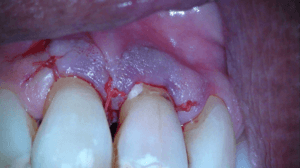

Na anesthesie volgde een flapoperatie om de pocket te openen. Al snel werd een breuk zichtbaar in het element. Maar hoe ver liep de barst door?

Voorzichtig verwijderden we alle granulatieweefsel en spoelden we het schoon. Wat we zagen had ik nog nooit eerder waargenomen. Er zat een min of meer circulaire barst wat eigenlijk een los zittend stukje dentine was.

Na het wegfrezen van het losse stukje vulden we het defect op met composiet. We werken de composiet af met fijne diamantjes en handscalers. Een superscherp geslepen handinstrument kan uitstekend worden gebruikt bij het afwerken van composietvullingen. Wel alleen vlak na het polymeriseren, dan is composiet nog te scalen.

Na polijsten hechtten we de flap en maakten we een afspraak voor een week later.

Toen we de patiënt terug zagen na drie maanden was het aspect van de 11 weer gezond. De pocket was gereduceerd, er was geen pusafvloed meer en het tandvlees zag er gezond uit.

Achteraf analyserend kunnen we stellen dat de situatie niet ideaal is. Er is een composietrestauratie gemaakt in het meest kwetsbare deel van het element en de restauratie ligt gedeeltelijk nog onder de gingiva. We hopen dat het lang goed gaat maar lekkage ligt op de loer natuurlijk en wellicht is het nodig om na een aantal jaren opnieuw een flapje te doen en de restauratie te vernieuwen.